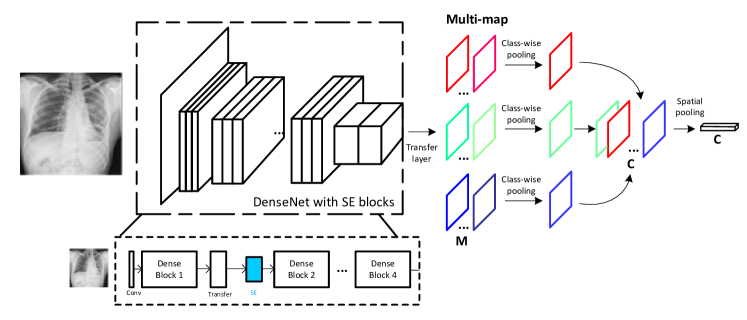

In this paper, we will present a novel weakly-supervised learning model to particularly overcome the aforementioned issues existing in previous works. The proposed model is able to classify thoracic diseases merely reading provided chest X-rays as well as to localize the disease regions on X-rays at pixel-level granularity. First, we harnessed the latest Fully Convolutional Network (FCN) alike model, i.e. DenseNet (Huang et al., 2017), as backbone network, because DenseNet has obviously shown its outstanding performance on generic image classification (Huang et al., 2017) and semantic segmentation (Jégou et al., 2017). Much beyond the original DenseNet, for the first time, we proposed to use the so-called ”Squeeze-and-Excitation” (SE) block (Hu et al., 2017), which aims to reinforce the sensitivity of our model to subtle differences between normal and lesion regions by explicitly modeling the channel interdependencies. Moreover, we incorporated the use of multi-map transfer layers to make our network perform better to learn disease-specific features that are highly related to disease modalities, e.g. ”Atelectasis” and ”Nodule” on chest X-ray. The last but not the least, we realized that the max-min pooling operators (Durand et al., 2017) perform better at spatially squeezing feature maps for each class of disease. Our major contributions in the paper are summarized as follows:

In this section, we will explicitly present the technical details of proposed framework. First, we illustratively discuss the advantages of DenseNet compared with other modern FCN models. Then, we individually discuss the roles of the three components that bring extra performance lift beyond DenseNet: squeeze-and-excitation block, multi-map transfer layer and max-min pooling operator. An illustration of proposed network architecture is in Fig. 2.

3.1. DenseNet for Chest X-rays

Fully convolutional network (FCN) (Long et al., 2015) has become one of the most successful deep learning frameworks for generic image classification and segmentation tasks. In (Wang et al., 2017), ResNet, a recent FCN alike model, delivered best classification accuracy on ChestX-ray8. A typical DenseNet (Huang et al., 2017) comprises multiple densely connected convolutional layers, which improve the flow of information and gradients through the network, making it converge better and mitigating gradient vanishing issue. Therefore, in many computer vision tasks, DenseNet has shown magnificently stronger capability of representation learning than ResNet. Then (Rajpurkar et al., 2017) fine-tuned a DenseNet that naturally preserves spatial information throughout the network. As well as on the purpose of a fair comparison, we particularly choose the publicly available DenseNet-121 model as backbone network 111https://github.com/pytorch/vision/blob/master/torchvision/models/densenet.py. As shown in Fig. 2, the backbone of the used DenseNet consists of four consecutive dense blocks. However, original DenseNet is incapable of handling the special issues in disease classification and localization on chest X-rays. For example, disease labels of ChestX-ray14 are highly noisy since they were generated from scanning report. Given a X-ray image corresponds to multiple disease types, it is still an open question how to make data selectively contribute to multiple classification and localization tasks.

The physical meaning of SE block for classification of chest X-rays comes from the hardly distinguishable illuminative contrast between lesion regions of different types of disease as well as the rest normal regions. Therefore, merely utilizing single feature map or independently processing multiple maps cannot provide enough informative features for disease classification. The workflow of SE block is given in Fig.3.

3.3. Multi-map Layer and Max-min Pooling

Because ChestX-ray14 offers multiple disease labels for most of X-rays, it is naturally required to perform a multi-class classification. Instead of generating a multi-hot score vector, which makes training difficult to converge, we were encouraged by good performance from introducing multi-map transfer layer, each output feature map of which corresponds to a particular disease class.

The last dense block generates feature maps with size as . Then we concatenate to it a multi-map transfer layer. The layer encodes the activation outputs of backbone network into individual feature maps for each disease class through convolution operation. Denote as the number of feature maps per class and as the number of classes, this transfer layer will achieve the output of size . When , it is reduced to a standard classification output of classes. The modalities are learned with only image-level label and the transfer layer maintains spatial resolution. The modalities aim at specializing to different class-related visual features.

To sufficiently utilize the provided multi-class label, we proposed a two-stage pooling layer to aggregate information on feature maps for each disease class. A standard class-wise average-pooling was first conducted to transform maps from to . As to spatial aggregation, we applied a recently proposed spatial max-min pooling (Durand et al., 2017) to globally extract spatial domain information. Because we find that global minimum information is also helpful for the medical image analysis, and the global minimum regions can act as a regularizer and reduce overfitting. The global maximum and minimum pooling are linearly combined in our model:

3.4. Comparison with CheXNet

The CheXNet (Rajpurkar et al., 2017) is a similar model that also uses DenseNet-121 as the backbone network. It removes the last linear layer of DenseNet and adds a convolutional layer as the transfer layer to convert the extracted 1024-channel feature maps into C-channel feature maps. To get the final -dimensional output, it then uses the global maximum pooling and the sigmoid function. Compare with the CheXNet, the proposed architecture completely remove the liner layer and is fully convolutional. Our model have significant modifications particularly for learning representations under a weak supervision. We highlight the significant modifications as below: